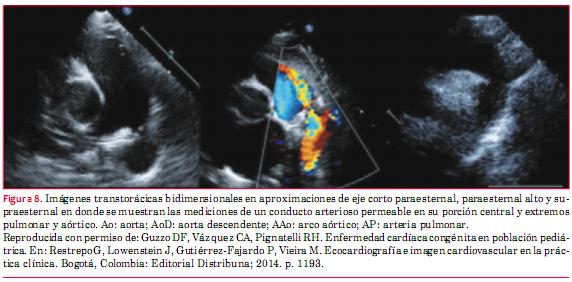

En la actualidad resulta extremadamente infrecuente que un ductus arterioso permeable (DAP) pase desapercibido hasta la vida adulta. El DAP dilata cavidades izquierdas, principalmente la aurícula izquierda (AI) y por ello un parámetro clásico en la valoración de la repercusión funcional del DAP es la relación AI/Aorta (Ao) cuyo valor máximo normal = 1,5. Se debe valorar también la función sistólica del VI. Finalmente, la valoración morfológica del ductus se logra mediante su visualización directa (figura 8 y figura 9 A y B). El enfoque ideal para este cometido suele ser paraesternal eje corto a nivel de los grandes vasos. En recién nacidos y niños habitualmente puede realizarse un barrido entre este corte y el supraesternal eje largo (paraesternal alto) que en adultos es más dificultoso. En este trayecto frecuentemente es posible obtener la imagen del ductus adecuadamente desplegado como para medir longitud y sección del mismo, aspectos de importancia si se plantea su cierre mediante dispositivos. También en este enfoque es donde habitualmente se logra un mejor alineamiento del chorro ductal con el haz del ultrasonido para registrar su flujo característico (figura 9 C y D). Finalmente, como en todo cortocircuito de izquierda a derecha, debe determinarse el QP/QS. Una comparación útil para la evaluación del tamaño ductal es su tamaño relativo respecto del tamaño de la rama izquierda de la arteria pulmonar (RPI). Un DAP cuyo diámetro supere 75% de la RPI se considera un DAP amplio; 50% mediano, y menos de 50% pequeño.